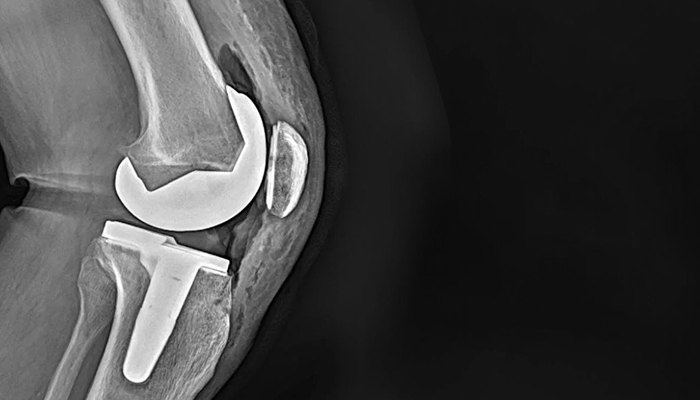

Gonarthrose (Prothèse totale de genou sur mesure – PTG)

Prothèse totale du genou, sur mesure